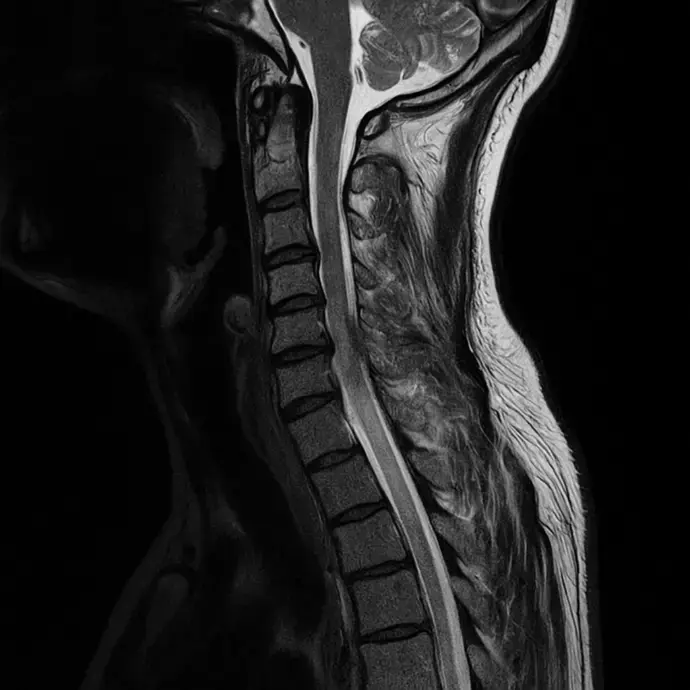

Una hernia discal cervical se produce cuando uno de los discos intervertebrales de la columna cervical se desplaza o se rompe, causando presión sobre los nervios cercanos. Esta condición puede generar dolor intenso en el cuello y los hombros, así como dolor irradiado hacia los brazos. Además, las personas con hernias discales cervicales pueden experimentar debilidad, hormigueo y pérdida de sensibilidad en los brazos o las manos.

Las hernias discales pueden ser el resultado de una lesión, o simplemente pueden desarrollarse con el tiempo debido al desgaste del disco intervertebral. Este tipo de afección suele generar dolor punzante o ardiente que no solo afecta el cuello, sino que puede extenderse a los brazos, causando molestias en las extremidades.